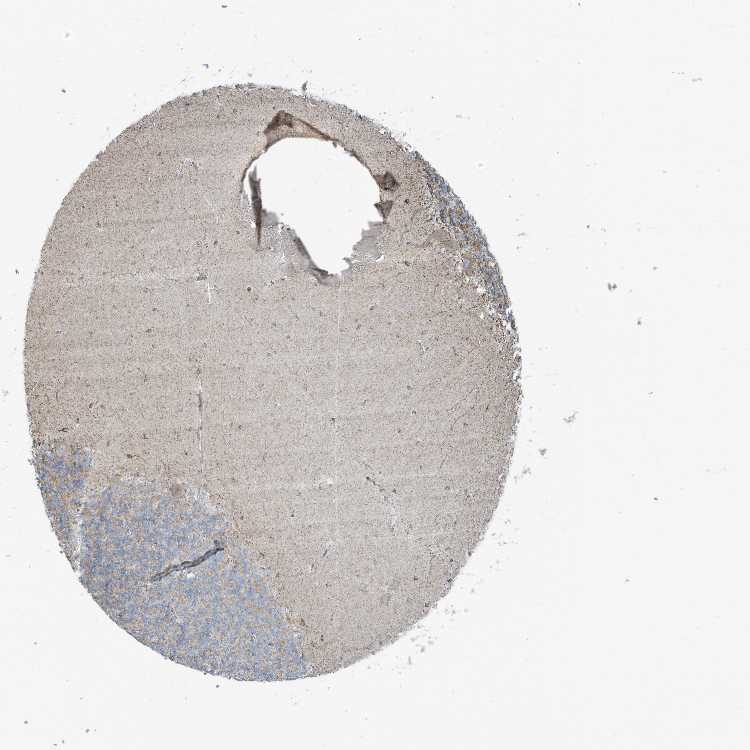

CEREBELLUM - Antibody stainingi

Antibody staining in the annotated cell types in the current human tissue is reported as not detected, low, medium, or high, based on conventional immunohistochemistry profiling in selected tissues. This score is based on the combination of the staining intensity and fraction of stained cells.

Each image is clickable and will lead to virtual microscopy that enables deeper exploration of all samples and also displays staining intensity scores, fraction scores and subcellular localization as well as patient and tissue information for each sample.

Antibody HPA028088Antibody HPA028631Antibody HPA030086

Purkinje cells Not detectedNot detectedLow

Cells in granular layer Not detectedNot detectedMedium

Cells in molecular layer Not detectedLowLow